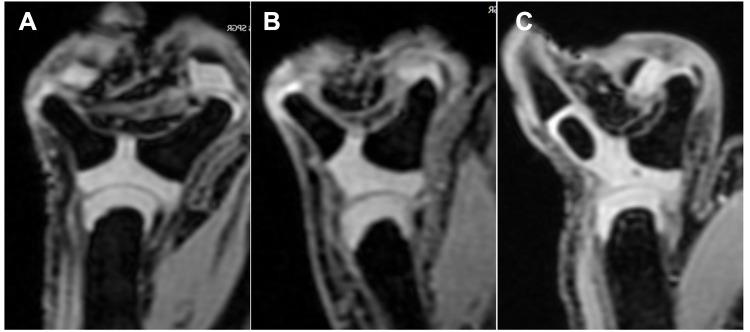

Our analysis demonstrated that MR imaging, especially the FS 3D SPGR sequence, yields better visibility of the cartilaginous structure and shows clearer joint characteristics that could not be detected by radiography. The abnormalities included a cartilaginous connection on the base of duplicated proximal phalanx, cartilaginous joint connection and the shape of articular cartilage on the head of metacarpal and soft tissue band. Radiologically encountered duplications at the MP joint level were successfully classified into six types based on the MRI-detected structural changes. The distribution of the six types was 17.7% (25/141) in type 1, 53.9% (76/141) in type 2, 2.8% (4/141) in type 3, 9.9% (14/141) in type 4, and 13.5% (19/141) in type 5.

This data showed that MR imaging provides practical information on the anatomic characteristics in radial polydactyly with bifurcation at the MP joint level that could aid surgical decision-making processes. Thus, the FS 3D SPGR sequence could be used as a MR imaging technique in radial polydactyly.